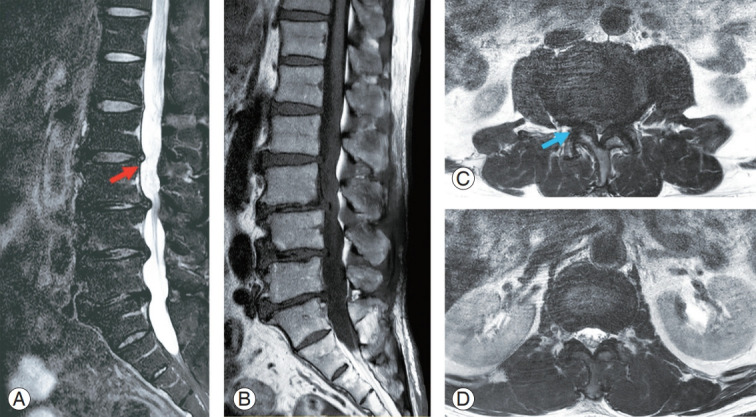

- MRI scan: shows nerves and soft tissues but requires lying still for a long time